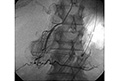

手術のできない高齢者―【全身への転移】進行性胃がんで全身に転移、手術と放射線治療ができない。抗がん剤と樹状細胞ワクチン療法を併用。胃がん部位に樹状細胞を直接注射、胃がんは顕著に縮小し転移部分でも縮小し進行停止。